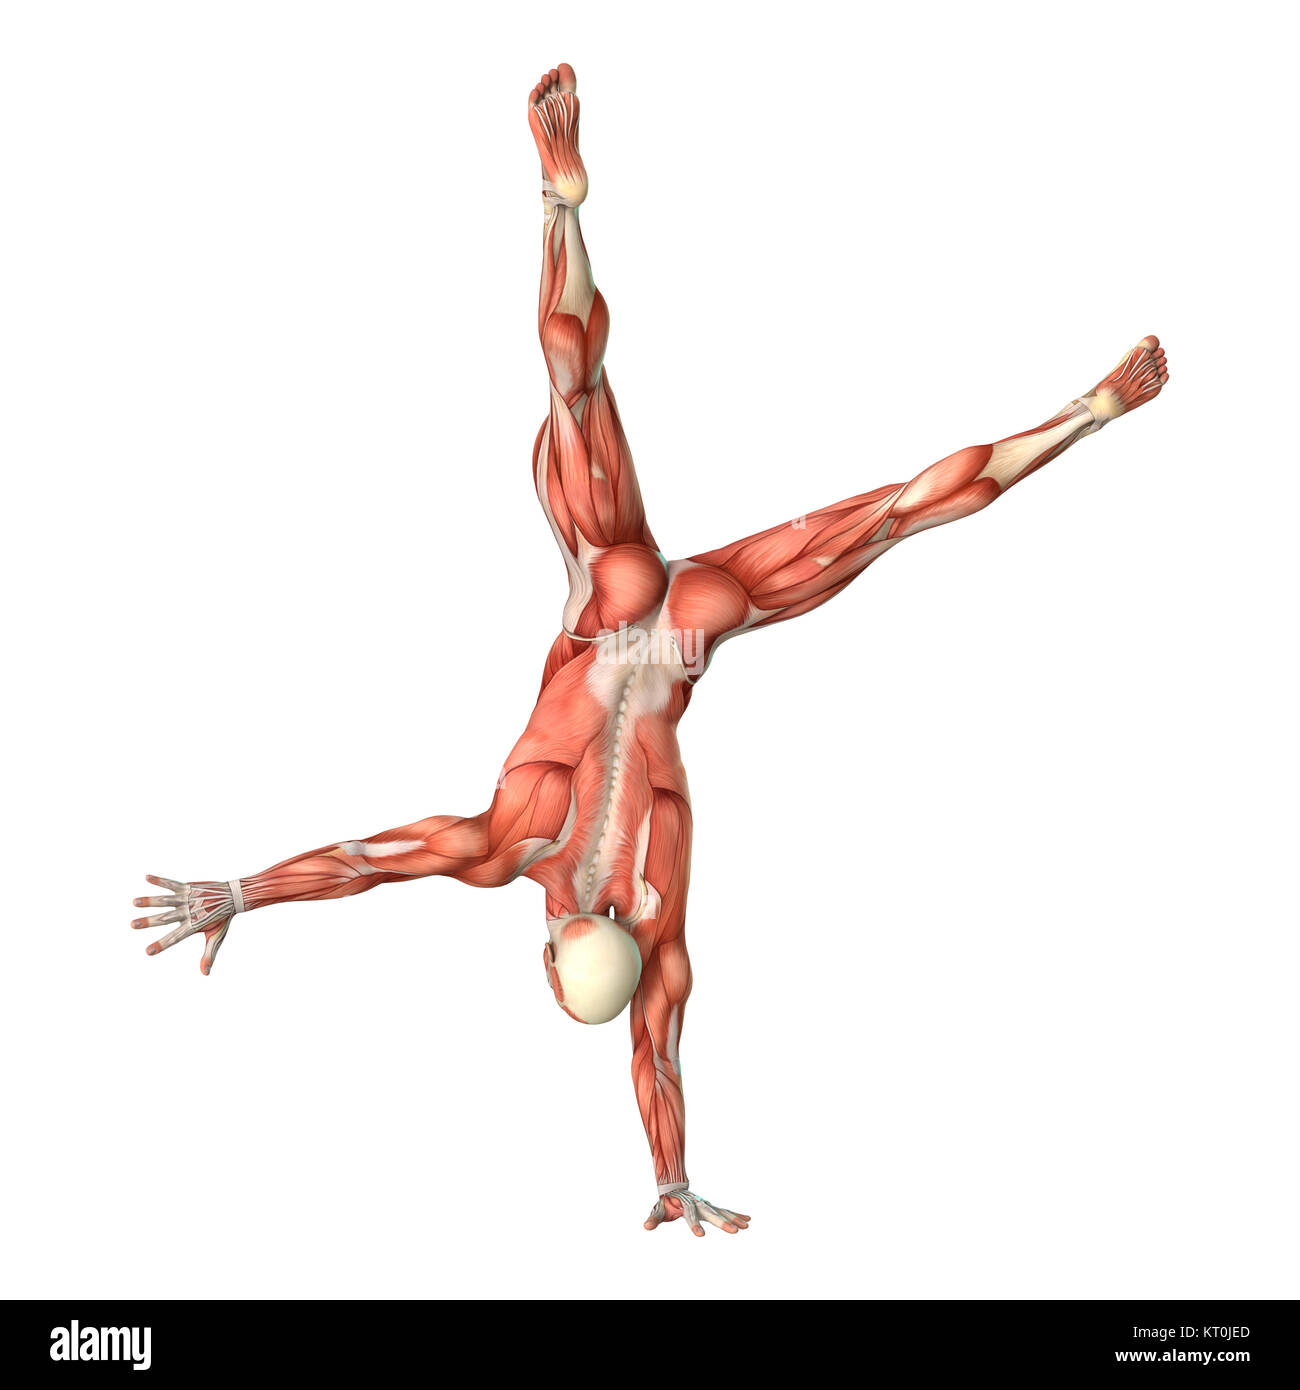

RFHAM8KJ–3D-Rendering einer männlichen Anatomie-Figur mit Muskeln Karte isolierten auf weißen Hintergrund

RMFX60TP–Menschen, Anatomie, Muskel, Körper, medizinische, Medizin, Illustration, Mann, Männlich, Gesundheit, muskulös, Wissenschaft, System, Biologie, Muskeln, ich